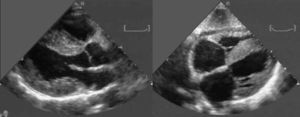

Evaluación cardiacaEcocardiogramaMediante ecocardiografía se puede encontrar diferentes signos de esta enfermedad, aunque los clásicos (Figura 3) sólo son propios de las fases avanzadas de la enfermedad38. El hallazgo más precoz es el engrosamiento de las pared ventricular izquierda (particularmente en ausencia de HTA), con evidencia de disfunción diastólica asociada38, 39. La presencia de paredes engrosadas, obviamente, tiene poca especificidad, ya que se encuentra también en otras afecciones cardiacas como la cardiopatía hipertensiva, la miocardiopatía hipertrófica y otras enfermedades infiltrativas del corazón (hemocromatosis, sarcoidosis, enfermedad de Fabry, etc.). La presencia de un patrón «granular» del miocardio se ha propuesto como un signo propio de esta entidad39, 40; sin embargo, su utilidad es limitada, ya que también aparece en otras causas de hipertrofia40, su sensibilidad es baja40 y sólo es valorable en ausencia de segundo harmónico. La disfunción diastólica, en cambio, es el hallazgo ecocardiográfico por antonomasia de esta enfermedad y está presente, en algún grado, en prácticamente todos los pacientes38. Los depósitos amiloides afectan a la distensibilidad del ventrículo, lo que se traduce en una disminución de la velocidad del flujo a través de la válvula mitral en la fase inicial de la diástole (disminución de la onda E) y un aumento en la fase tardía (aumento de la onda A) por mayor dependencia en la contracción auricular en el llenado ventricular. La disminución en la relación E:A es un signo precoz de la afección. Sin embargo, según los ventrículos se vuelven menos distensibles, la presión intrauricular aumenta y del mismo modo la velocidad inicial de llenado, dando lugar a una seudonormalización de la relación E:A. Finalmente, en fases avanzadas, lo habitual es encontrar un patrón de llenado restrictivo, con un tiempo de deceleración de la onda E reducido y baja velocidad de la onda A, unido a anormalidades en el flujo de las venas pulmonares41.

Figura 3. Ecocardiograma característico de paciente con amiloidosis por transtiretina. Izquierda: eje paraesternal longitudinal. Derecha: plano subcostal. Obsérvese el grosor aumentado del septo interventricular, ambos ventrículos y el septo interauricular. También es evidente un derrame pericárdico ligero. Cortesía del Laboratorio de Imagen Cardiaca del Policlinico S. Orsola-Malpighi, Bolonia, Italia.

El uso de Doppler tisular y strain rate puede ser de especial interés en esta enfermedad. Así, mediante Doppler tisular se encuentra reducción en las velocidades diastólicas tanto en fases tempranas como tardías de la enfermedad, y permite su identificación incluso cuando prácticamente no hay hipertrofia ventricular42. El strain rate permite documentar precozmente la afección cardiaca al detectar un deterioro en la función contráctil longitudinal43, y sus hallazgos se han relacionado incluso con el desarrollo posterior de IC y con la posibilidad de diferenciar distintos tipos de amiloidosis44.

Otros hallazgos ecocardiográficos incluyen la presencia de valvas engrosadas, derrame pericárdico ligero, dilatación biauricular y engrosamiento del septo interauricular. Aunque todos estos signos se describen en un 40-60% de los pacientes (con excepción del engrosamiento del septo interauricular, que es menos frecuente), se trata de series muy seleccionadas con pacientes que se encuentran en fases avanzadas de la enfermedad. La disfunción sistólica, por su parte, tampoco aparece hasta fases avanzadas.